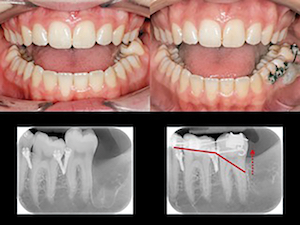

Quand l’objectif est l’ingression d’une dent, 4 mini-vis posées à ses quatre coins peuvent servir d’ancrage à des chainettes de traction reliées à des boutons ou des brackets collés sur sa couronne.

Ici pour l’ingression de 47 les mini-vis n’ont pu être posées en distal, 48 ayant été extraits le même jour. Le problème a été contourné par l’utilisation d’un sectionnel d’ingression à partir de mini-vis positionnées plus en mésial.